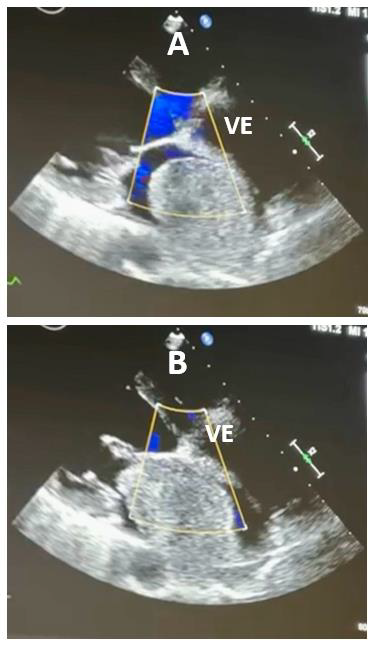

Ao exame: Lúcida, orientada, emagrecida (perda de 10kg em 3 meses), acianótica, corada. Temp: 37,2°C. FC: 102 bpm, PA: 100x64 mmHg, SatO2: 96%. MVUA com crepitação fina nas bases. Ritmo cardíaco regular, em 2T, BNF, com ruído protodiastólico de baixa frequência audível no foco mitral em decúbito lateral esquerdo, seguido de um sopro diastólico 2+/6+ no mesmo foco. Abdome e MMII sem alterações. ECG com taquicardia sinusal. Ecocardiograma transtorácico revelou as imagens A e B abaixo.

Considerando as duas imagens ecocardiográficas, assinale a opção que provavelmente corresponde ao ruído protodiastólico de baixa frequência descrito no exame físico.